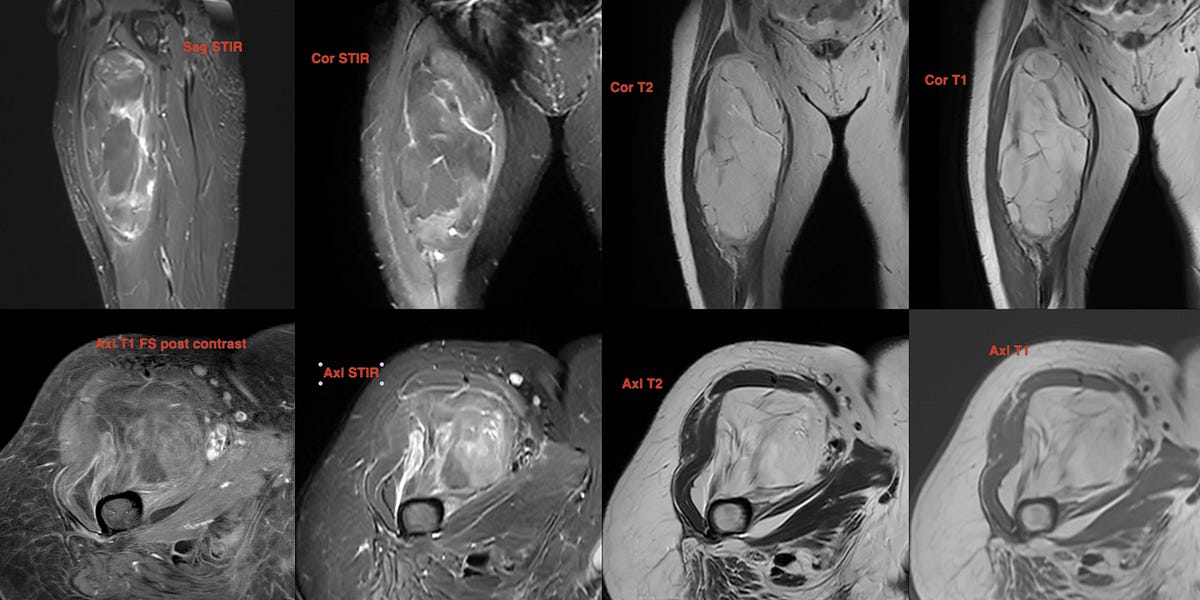

66-years old man presented with a mass in the spleen involving the tail of the pancreas.

Findings: Large splenic mass involving tail of pancreas

Lesion Biopsied: Splenic mass

Size of Lesion: > 30 mm